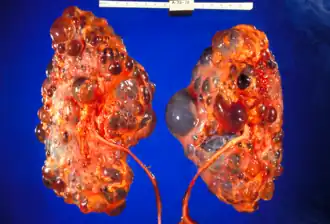

Reins polykystiques gravement affectés enlevés au moment de la transplantation

Description de cette image, également commentée ci-après